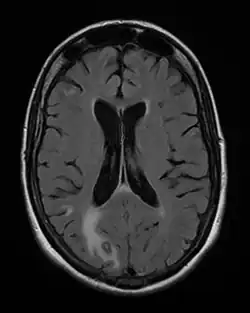

MRI: Cerebral toxoplasmosis with primary involvement in the right occipital lobe (at left and below of the image). 48-year-old woman with AIDS

Toxoplasmosis in humans is diagnosed through biological, serological, histological, or molecular methods, or by some combination of the above.[62] Toxoplasmosis can be difficult to distinguish from several other conditions, especially ones that are common in HIV/AIDS and immunocompromised patients, and can cause central nervous system problems and brain lesions.[68] Toxoplasmosis is most commonly mistaken for primary central nervous system lymphoma, both conditions cause lesions in the brain, but in about 50-80% of cases the lesions appearances can be very similar on imaging, and exist in an area of the brain that makes biopsying too risky, however the main difference is lymphoma typically causes a single lesion in the subependymal region, and toxoplasmosis causes multiple lesions scattered through the basal ganglia.[69] Other conditions that can present as toxoplasmosis on a differential diagnosis are metastatic brain lesions, progressive multifocal leukoencephalopathy[70], CNS tuberculosis[71], bacterial or fungal brain abscess, cytomegalovirus (CMV),[72] and herpes simplex encephalitis.[68][73]